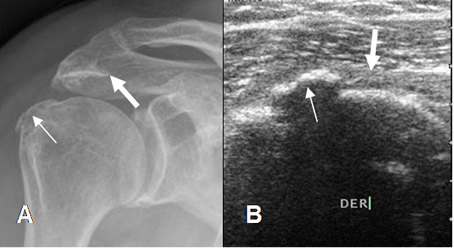

Fig 84. Cambios degenerativos.

A: Rx AP. Se observan osteofitos en el borde inferior del acromión (Flecha gruesa) y sobre la tuberosidad mayor (Flecha delgada).

B: Ecografía coronal. Zona ecogénica en el borde superior del húmero, que corresponde a osteofito, (Flecha delgada), el cual comprime y adelgaza el tendón del supraespinoso. (Flecha gruesa).